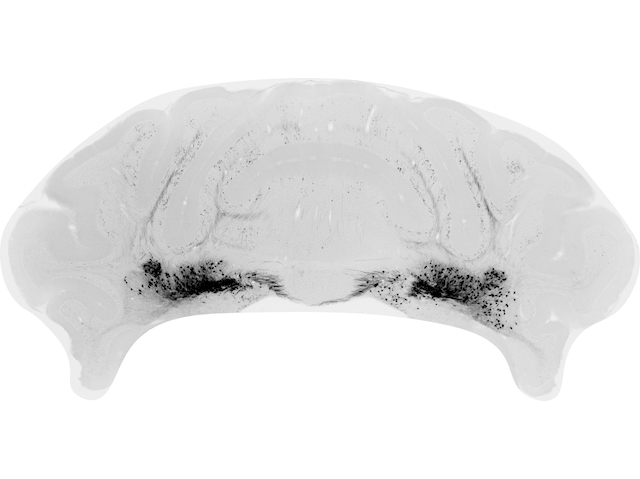

At the back of your skull, about level with your ears, sits your cerebellum. It's only the size of a Mars bar, but it contains more neurons than the rest of your brain combined. For a long time, scientists thought the cerebellum was primitive, only controlling how the body moves, but recent work has shown it's more complex. Here, we see a slice of a mouse cerebellum highlighting nuclei neurons (black) important for motor control. Researchers showed that if these cells can't signal, mice develop severe movement problems. However, the brain compensates for this damage, so adult mice show few symptoms. In contrast, neurons in the cerebellar cortex seem to control social behaviours instead of movement, and the brain can't compensate for their damage. These results reveal the surprising complexity of the cerebellum and help us better understand how the brain copes with damage before birth.